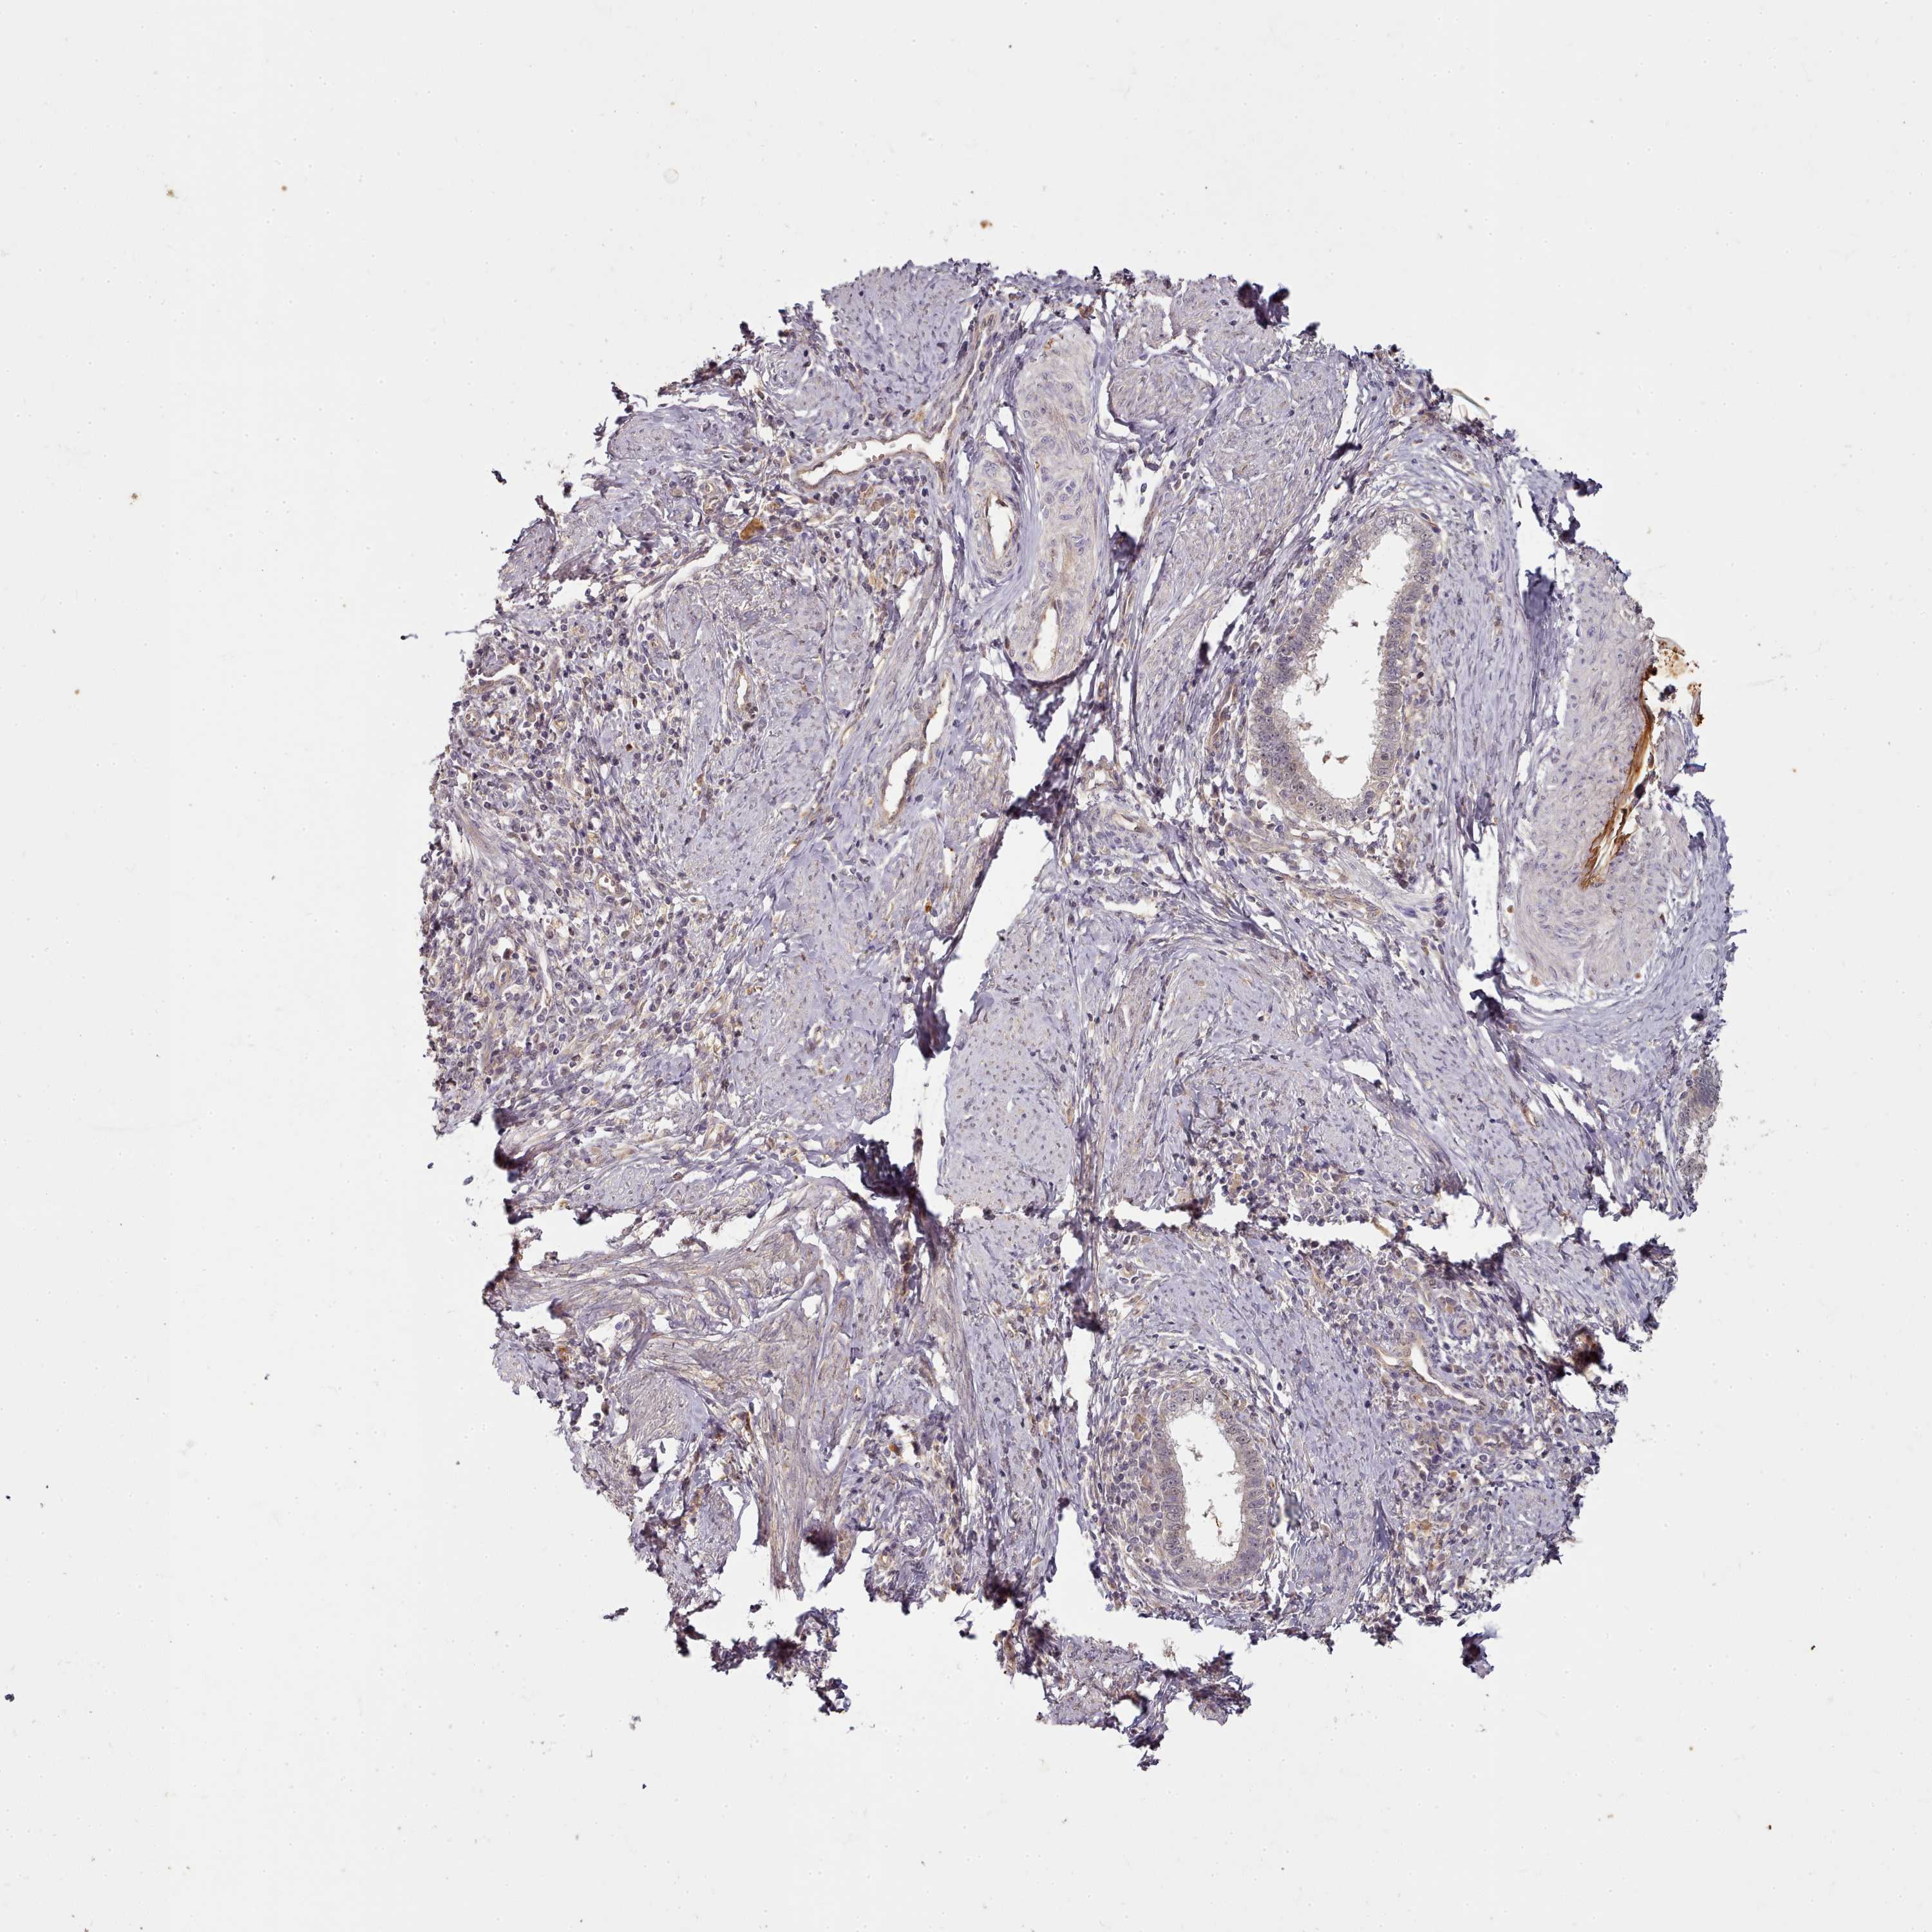

CERVICAL CANCER - Protein expressioni

A mouse-over function shows sample information and annotation data. Click on an image to view it in a full screen mode. Samples can be filtered based on level of antibody staining by selecting one or several of the following categories: high, medium, low and not detected. The assay and annotation is described here.

Note that samples used for immunohistochemistry by the Human Protein Atlas do not correspond to samples in the TCGA dataset.

Antibody stainingi

Antibody staining in the annotated cell types in the current human tissue is reported as not detected, low, medium, or high, based on conventional immunohistochemistry profiling in selected tissues. This score is based on the combination of the staining intensity and fraction of stained cells.

Each image is clickable and will lead to virtual microscopy that enables deeper exploration of all samples and also displays staining intensity scores, fraction scores and subcellular localization as well as patient and tissue information for each sample.

Antibody HPA038604

Antibody CAB025607

Squamous cell carcinoma, NOS

Adenocarcinoma, NOS